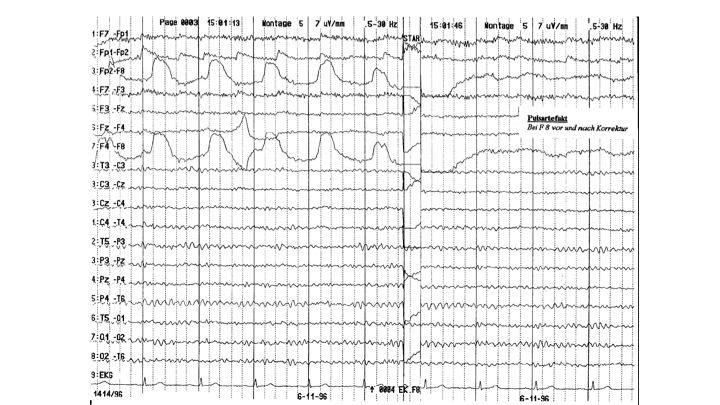

Artefakte im EEG | 25.65 zurück | weiter